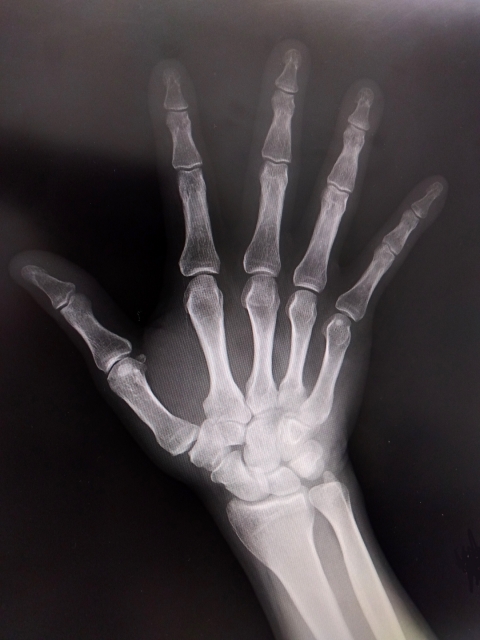

■ 橈骨遠位端骨折とは

前腕の骨である「橈骨」の手首側(遠位端)に起こる骨折です。

転倒時に手をつくことで発生することが多く、特に日常生活やスポーツ中の転倒で起こります。

■ 主な種類

- ・コーレス骨折

手のひら側に手をついて起こる、最も多いタイプ - ・スミス骨折

手の甲側に手をついたり、屈曲位で起こる比較的稀なタイプ

■ 関連する組織

- ・橈骨・尺骨

- ・骨膜

- ・手関節靱帯

- ・屈筋腱・伸筋腱

- ・正中神経・橈骨神経